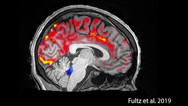

Getting plenty of deep, restful sleep is essential for our physical and mental health. Now comes word of yet another way that sleep is good for us: it triggers rhythmic waves of blood and cerebrospinal fluid (CSF) that appear to function much like a washing machine's rinse cycle, which may...